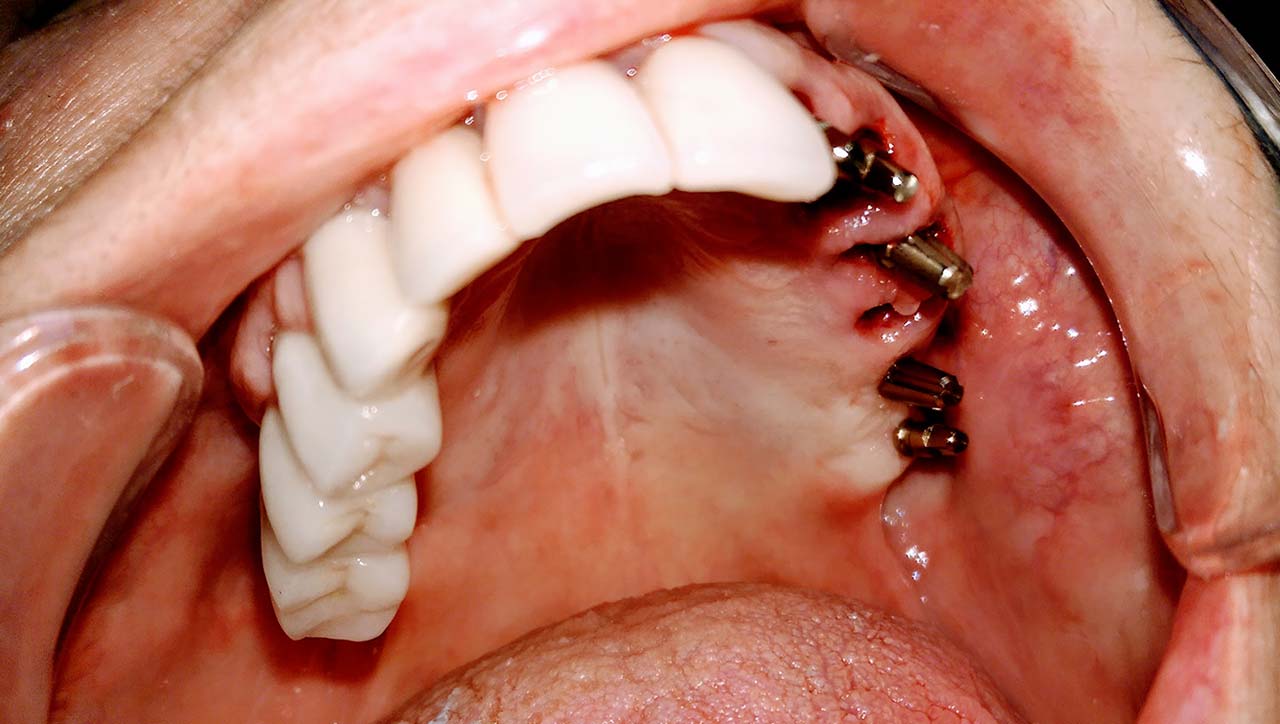

Implantáció törött, rossz fogak helyett

A rossz fogakat és a mozgó, törött fogakon álló hidat a fogakkal együtt eltávolítottuk. A fogak helyére, és a stratégiailag jó csontállományú területekbe azonnal behelyezett implantátumokra 3 nap múlva elkészítettük az esztétikus, rögtön terhelhető ideiglenes hidat.